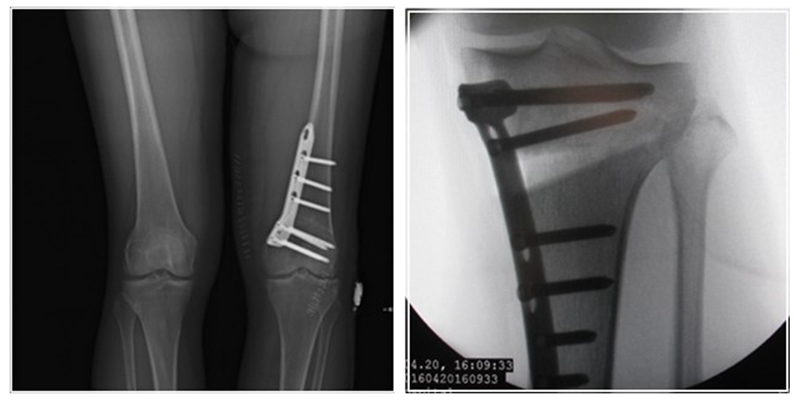

术后影像

患者二,女性,膝外翻,膝外侧疼痛。通过做畸形分析后发现,该患者同时存在股骨侧畸形、胫骨侧畸形和关节内畸形(LDFA=82°,MPTA=104°,JLCA=6°)。